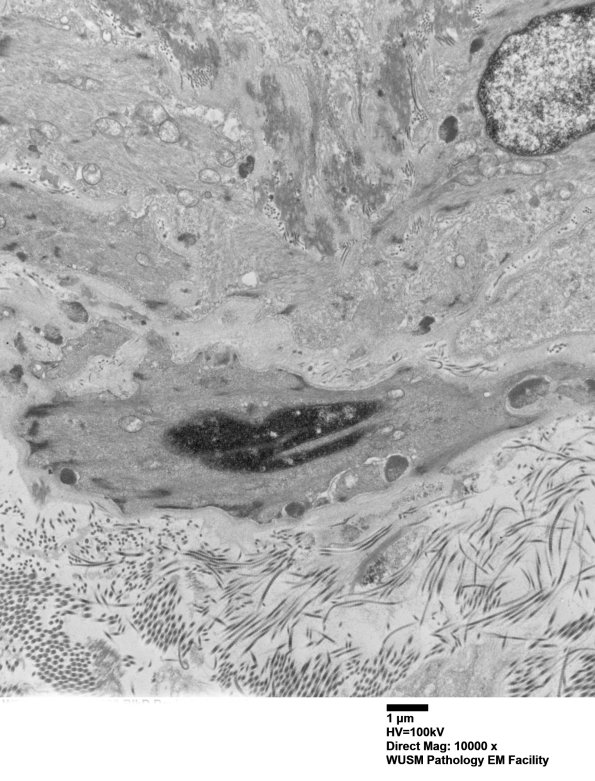

11C3A This smooth muscle cell is on the outer aspect of the arteriole. (electron micrograph)